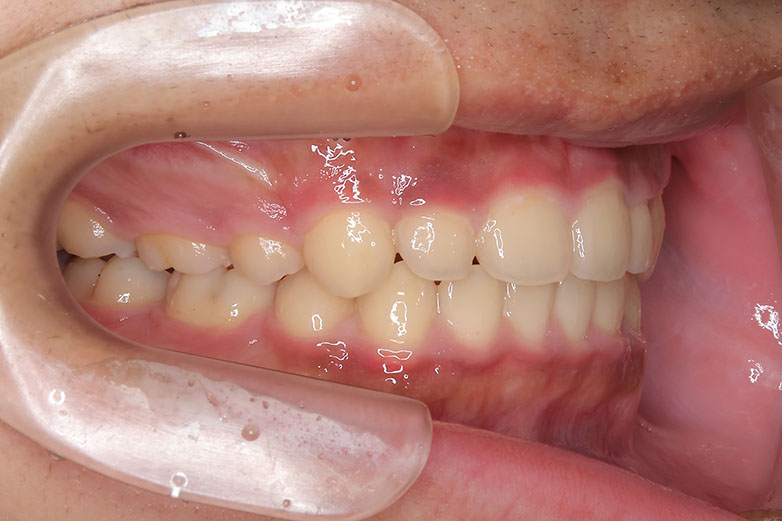

右上の前歯が生えてこない事を気にされ来院されました。 レントゲン写真から、上顎正中に過剰歯が埋伏していることが原因でしたので、抜歯して経過観察。 遅れて、無事に生えてきました。 もし、自然に生えてこない場合は、開窓して、引っぱり出します。(廷出) 状態により、引っぱり出せない場合もあります。 将来的にスペース不足により、上下顎前臼歯部に重度の叢生(がたつき)が予測できますので、がたつきを減らすために、小児矯正で側方拡大を行いました。 小児矯正で側方拡大を行ってもスペースが足りない場合(著しくスペース不足の場合)は、がたつき(叢生、八重歯)が残ります。 残ったがたつき(叢生)は、本格矯正ですべて生え変わった中学生から治せば問題ありません。 来院間隔が平均で1.5カ月でしたので半年ほど治療期間が長いです。